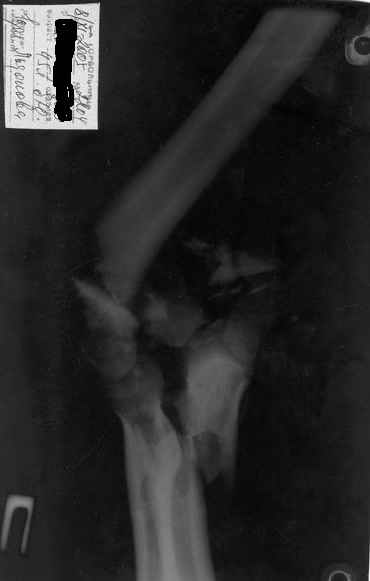

Здравствуйте, коллеги.Мужчина, 45 лет, ДТП 24.10.05. На сегодня неврологических расстройств правой кисти нет, отека нет, движения в правом плечевом и в правой кисти в полном объеме. Правый локтевой сустав сгибани 110*, разгибание 140*, наружняя ротация предплечья 45*, внутренняя 45*. Укорочение правого плеча 4 см. Больной просит у меня совет, стоит ли ему стремиться к эдопротезированию локтевого сустава.Я, к сожелению, не видел ни одного больного после эндопротезирования локтевого сустава.-- С уважением,Анатолий Борзунов